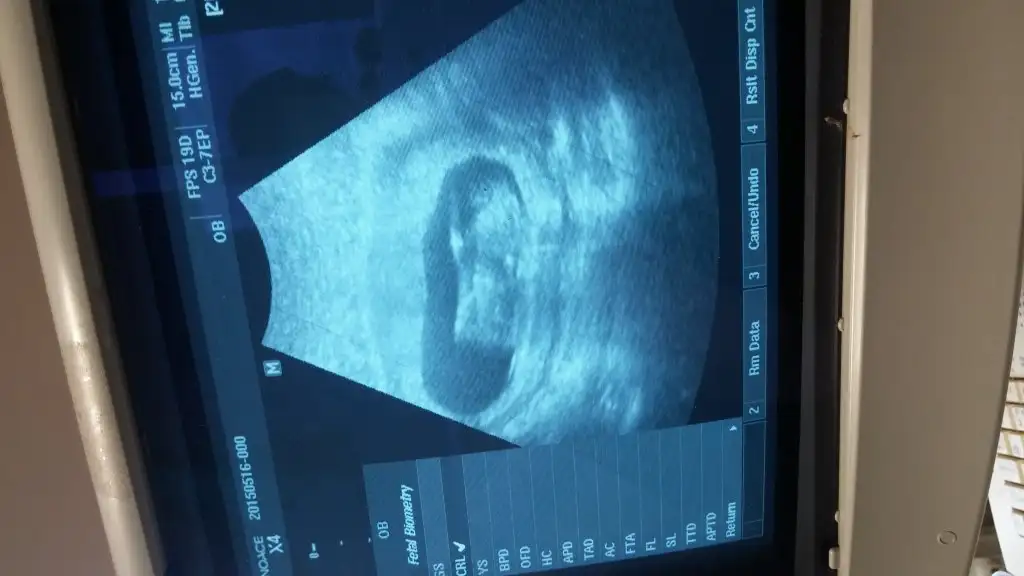

bu da kız gibi ama tam belli değil. kız gibi görünen erkeğe dönen nublar var paralel ama uzun ona da benziyo sanki yine de kız dicem bakalım tutcak mı öğrenince yazarsınız12+3 günlük teyzeleri,cinsiyet tahmini bizede yaparmısınız???Eki Görüntüle 1545346

bu da kız gibi ama tam belli değil. kız gibi görünen erkeğe dönen nublar var paralel ama uzun ona da benziyo sanki yine de kız dicem bakalım tutcak mı öğrenince yazarsınız